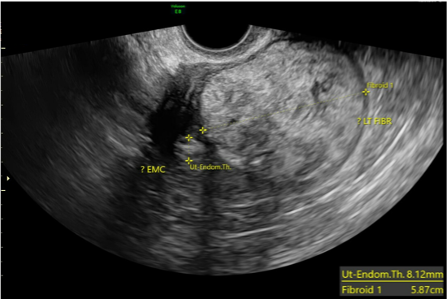

A female patient in her 70s presented to her gynecologist complaining of intermittent lower abdominal pain, bulk symptoms, cramping, and vaginal spotting for 6 months. Her medical history is significant for breast cancer diagnosed over 10 years ago and class II obesity. The patient underwent a pelvic ultrasound which revealed an 8 mm endometrial stripe and a 7 cm x 5 cm left uterine mass [figure 1] deemed a uterine fibroid. Endometrial biopsy showed carcinosarcoma and the patient subsequently underwent hysterectomy and bilateral salpingo-oophorectomy. The tumor measured 11.5 x 10.0 x 3.1 cm and was semi-firm, tan-white, friable, and exophytic on gross examination. F myometrial invasion into the serosa and involvement of bilateral ovaries and fallopian tubes was identified. [figure 2]

Figure 1. Pelvic ultrasound demonstrates a 7.82 x 5.87 cm mass with an 8.12 mm thickened endometrial stipe.